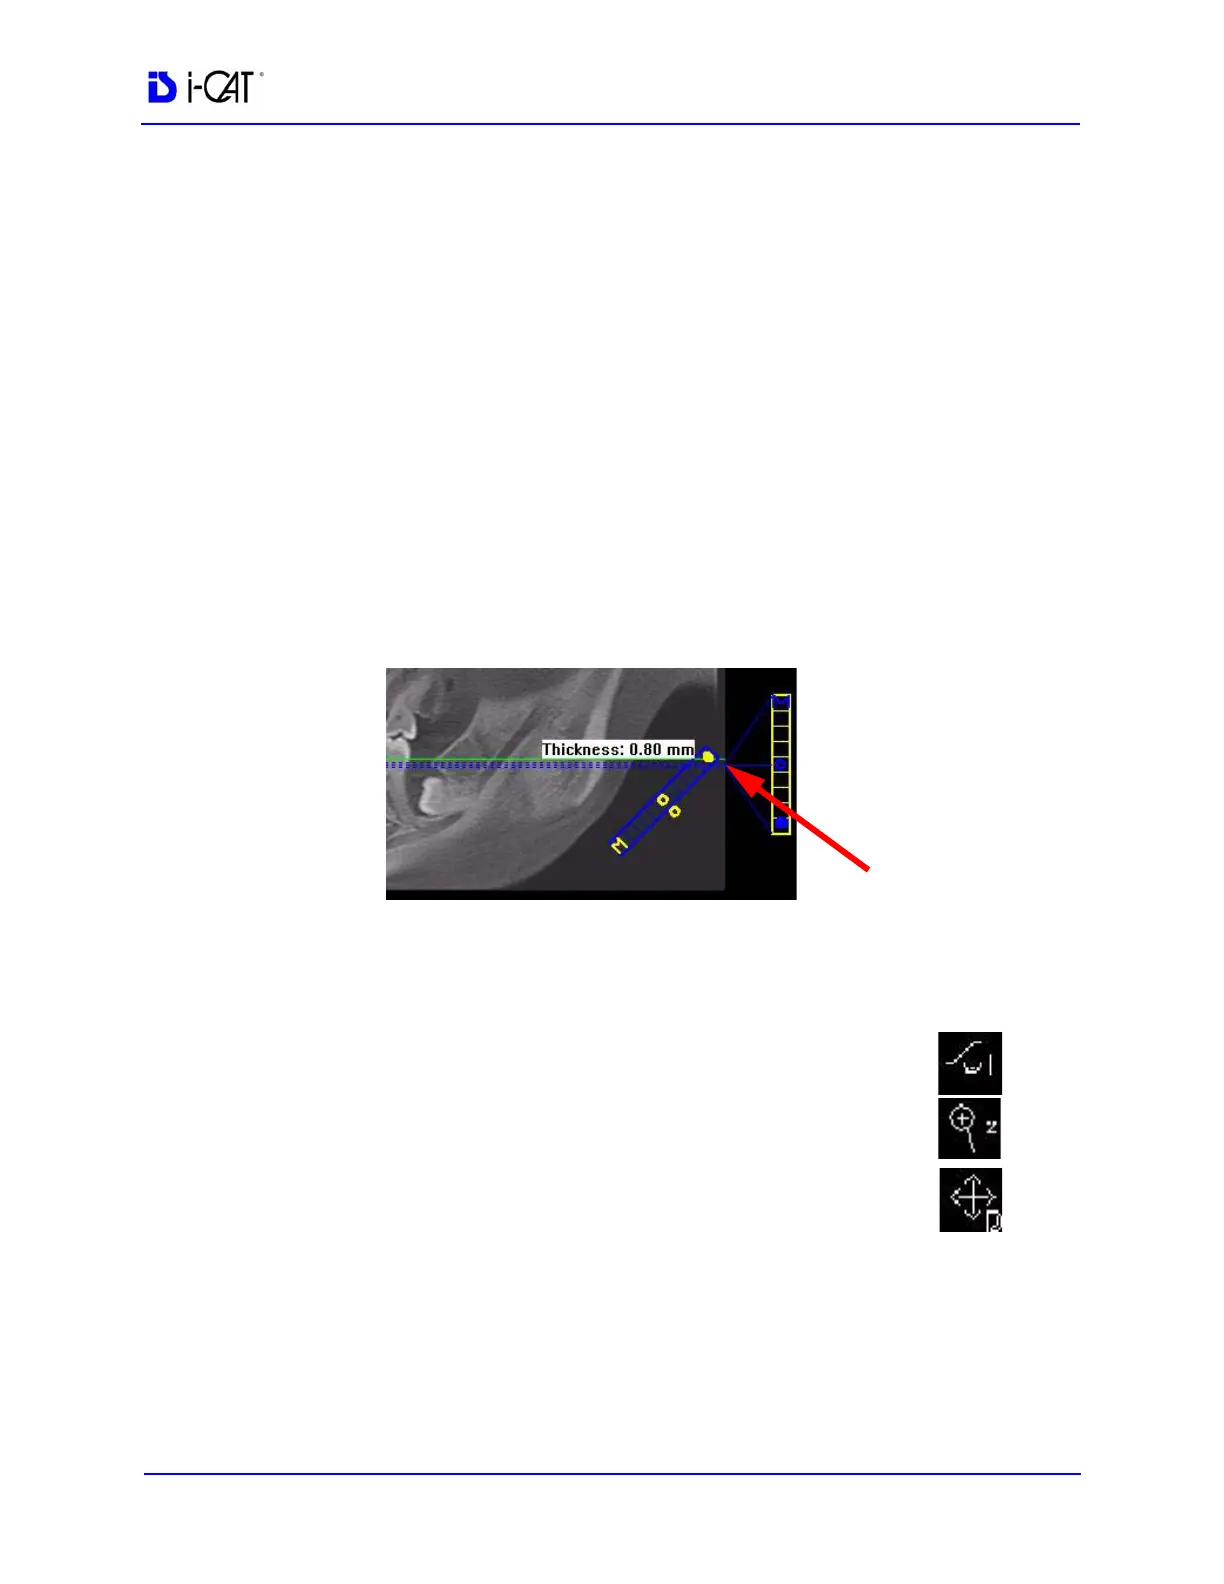

2. On the panoramic map view, click the solid dot on the diagonal

slice control to check the slice thickness. If thickness is over 1.0

mm (1.2 mm for voxel sizes greater than or equal to 0.3 mm),

drag the solid dot down to reduce the slice thickness. Slice must

be no thicker than stated above to be able to mark points in the

panoramic map view.

DIAGONAL

SLICE CONTROL